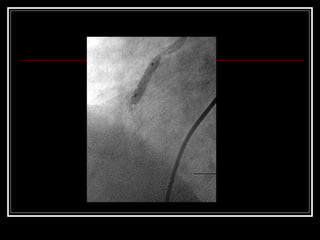

Angioplastía Percutánea

• Técnica que permite reabrir las arterias carótidas

obstruidas.

•Se lleva a cabo cuando hay una obstrucción del 70

% o mayor.

• Se realiza introduciendo un pequeño balón en el

sitio del vaso que presenta estrechamiento.

• Luego, el balón se infla a presión hasta que la

arteria alcance el diámetro normal.

• Técnica quepermite reabrir las arterias carótidas obstruidas. •Se lleva a cabo cuando hay una obstrucción del 70 % o mayor. • Se realiza introduciendo un pequeño balón en el sitio del vaso que presenta estrechamiento. • Luego, el balón se infla a presión hasta que la arteria alcance el diámetro normal.